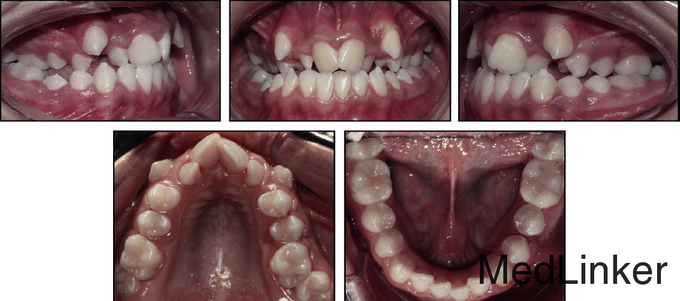

女,14岁,牙齿排列非常不整齐,微笑时牙弓特别狭窄,要求解决.小时候有鼻呼吸道的阻塞及过敏性鼻炎,可能是导致错合的病因。

直面型,上颌严重横向不调伴严重拥挤(拥挤度17mm),前牙及双侧后牙反合,下牙列重度拥挤,左侧磨牙I类,右侧磨牙II类关系,双侧尖牙II类关系。劲椎片可见其已过生长发育期